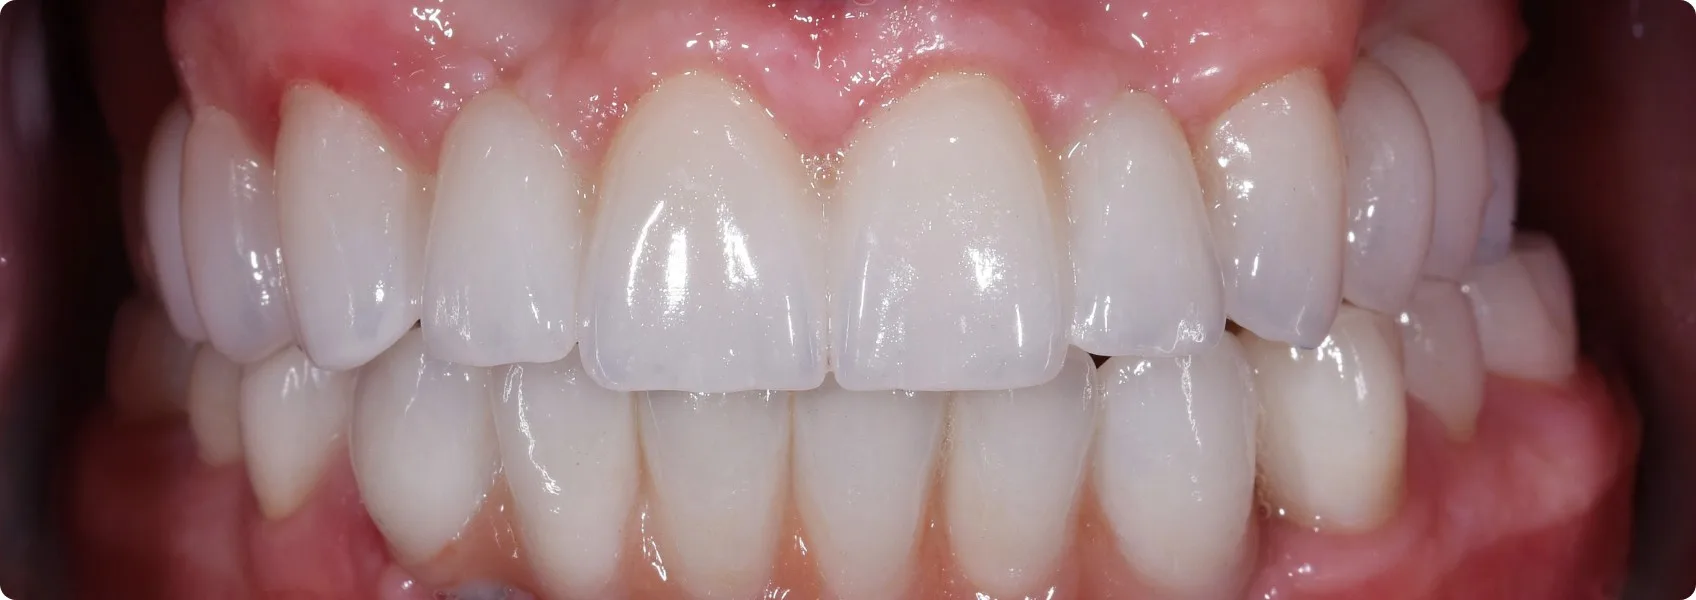

W wyniku dysplazji ektodermalnej zęby Pacjenta nie wykształciły się prawidłowo: były niewielkie, niektóre o stożkowatym kształcie, występowały między nimi liczne przerwy.

Dzięki współczesnej stomatologii potrafimy jednak skutecznie zrekonstruować to, czego natura nie wykształciła prawidłowo.

Ten przypadek dowodzi, że nawet w najtrudniejszych, uwarunkowanych genetycznie sytuacjach, dzięki bezkompromisowemu planowaniu, współpracy specjalistów i rozbudowanym protokołom leczenia, przywracamy pełną funkcję narządu żucia i naturalne piękno uśmiechu.